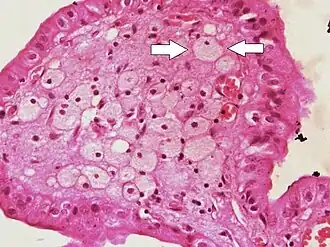

Foam cells (one indicated by arrows) visible in the finger-like projections into the gallbladder lumen in a case of cholesterolosis

Foam cells, also called lipid-laden macrophages, are a type of cell that contain cholesterol. These can form a plaque that can lead to atherosclerosis and trigger myocardial infarction and stroke.[1][2][3]

Foam cells are fat-laden cells with a M2 macrophage-like phenotype. They contain low density lipoproteins (LDL) and can be rapidly detected by examining a fatty plaque under a microscope after it is removed from the body.[4] They are named because the lipoproteins give the cell a foamy appearance.[5]